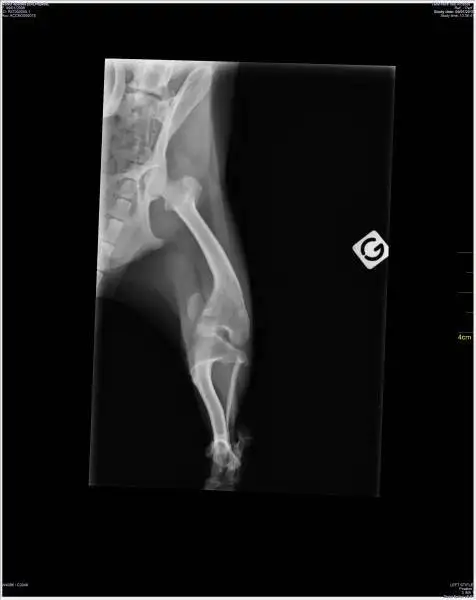

Le cas le plus évident est le traitement des fractures des os longs (fémur, tibia, humérus, radius, ulna, par ex.) mais aussi de certaines pathologies articulaires (arthrose par ex.) ou ligamentaires (rupture du ligament croisé antérieur par ex.).

Nous disposons d'un panel d'ancillaires de pose d'implants orthopédiques varié dont les très récents implants de vis à tête de verrouillage (technologie LCP) permettant de traiter la plupart des affections orthopédiques .